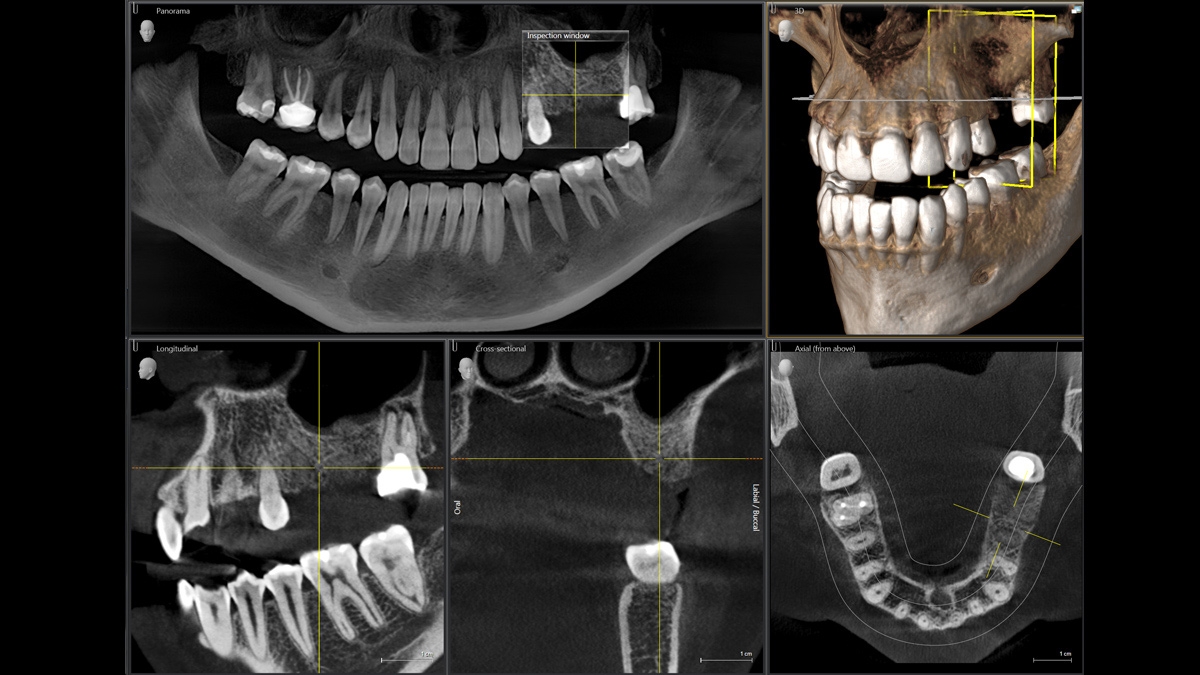

Orthophos SL ile, uygulamanız çeşitli tedavi durumları için son derece iyi hazırlanmıştır. 2D tarafında, çığır açan DCS sensörü ve SL teknolojisi, panoramik görüntüleme açısından çok yüksek talepleri olan kullanıcıların gereksinimlerini karşılar. 3D'de, 8 cm x 8 cm veya 11 cm x 10 cm ses birimi arasında (şimdi veya ilerde) karar bir verebilirsiniz. Her iki ünite de çeşitli kolimasyonlar (hizalamalar) sunar.

Öncü Sidexis 4 görüntüleme yazılımına sahip Orthophos SL çeşitli yenilikçi tedavi çözümlerine erişmenizi sağlayacaktır. Orthophos SL 3D'ye, istediğiniz zaman bir sefalometrik kol eklenebilir.